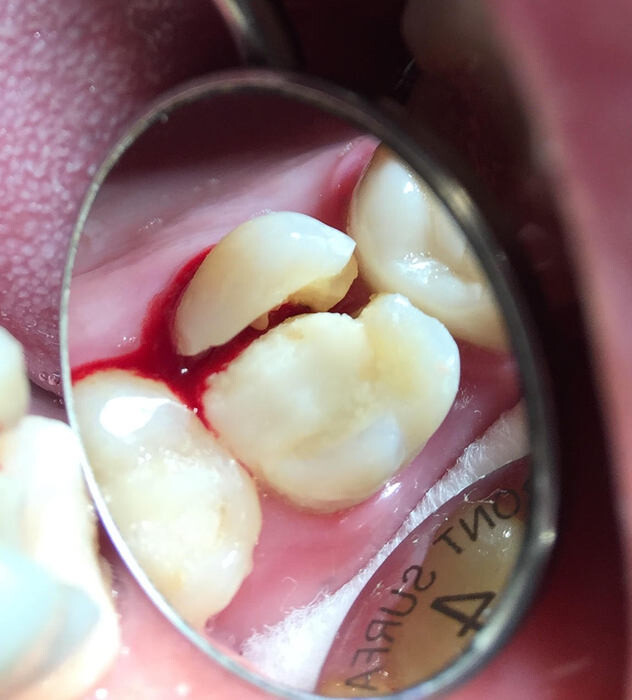

What To Do if You Have a Cracked Molar

When it comes to eating, your molars do a lot of work. So it’s no surprise that if one of them gets a crack, it’s a big deal. You need them. Here’s a look at cracked tooth symptoms and cracked tooth treatment if you’ve cracked one of your molars.

If the crack has gone beyond the enamel, treatment will be needed to prevent problems such as an infection or a deeper fracture. Treatment will be based on the severity of the crack. Your dentist may recommend a crown, root canal, or tooth extraction. If your dentist thinks a crown is best, a filling material can repair the crack. If the inside of your tooth is damaged, your dentist may suggest a root canal to remove the damaged tissue. The root canal will be recommended if there’s an infection. Tooth extraction is the last case scenario if the tooth is too far gone and can’t be saved.